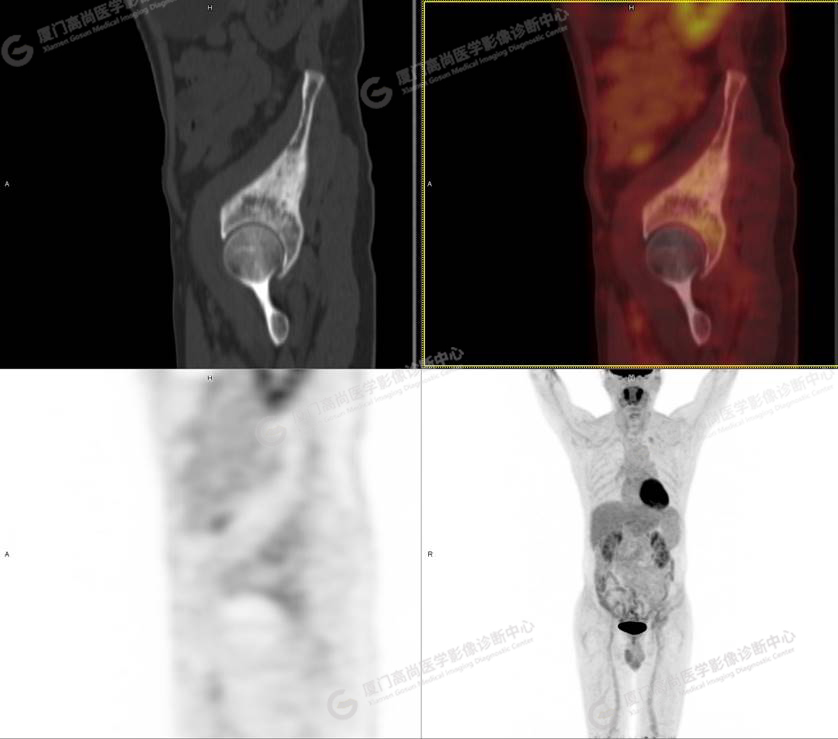

病史摘要1

60歲的L先生,因“左側(cè)臀部疼痛伴行走困難3月余”就診,外院核素骨顯像示:左側(cè)髂骨顯像劑增加,考慮惡性病變可能。同時實驗室檢查發(fā)現(xiàn)腫瘤指標(biāo)糖類抗原724稍增高。談癌色變!驚恐的L先生選擇了腫瘤檢查的核武器——PET/CT以探明虛實。

PET/CT檢查

PET/CT所見:左側(cè)髂骨、髖臼及恥骨骨質(zhì)密度不均勻增高,CT值約594Hu,邊緣模糊,放射性攝取輕度增高,SUVmax 2.79,周圍軟組織未見明顯異常。

影像診斷: L先生和Z女士的骨骼改變,指向了同一個疾?。汗抢w維異常增殖癥。